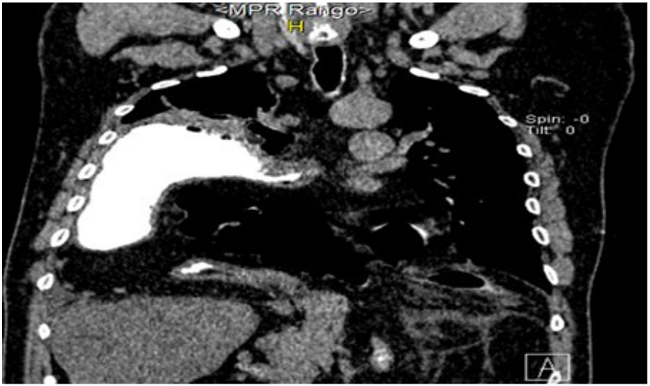

Tomografía computarizada de tórax y abdomen en la cual se observa la presencia de todo el estómago en el hemitórax derecho acompañado de la presencia de parte del colon transverso y epiplón mayor, los cuales se han herniado a través del hiato esofágico (Figura 2).

Con el uso de la TACM, en particular con reconstrucciones multiplanares, fue posible caracterizar con detalle la anatomía de la hernia y definir de qué tipo se trataba, establecer que existía rotación gástrica y evaluar la herniación de otras estructuras abdominales además del estómago como el colon transverso y epiplón mayor y, por último, establecer la ausencia de complicaciones como vólvulo o perforación gástrica.